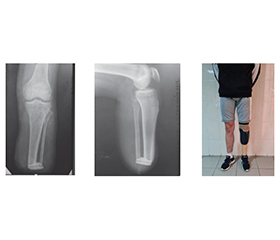

Актуальність. Повномасштабні воєнні дії супроводжуються зростанням кількості поранених із тяжкими ушкодженнями кінцівок, що часто потребують ампутацій. Незважаючи на вдосконалення хірургічних технологій, у значної частини пацієнтів після ампутації нижніх кінцівок формуються патологічно змінені кукси, що ускладнює їх протезування та подальшу реабілітацію. Мета: підвищення ефективності реконструктивно-відновного лікування пацієнтів із дефектами ампутаційних кукс нижніх кінцівок після бойової травми шляхом удосконалення способів ампутаційної пластики. Матеріали та методи. Проведено клінічне обстеження та хірургічне лікування 126 пацієнтів із дефектами ампутаційних кукс гомілки, серед яких переважали посттравматичні ураження, зумовлені мінно-вибуховими та вогнепальними пораненнями. Виконано 137 реконструктивних оперативних втручань, серед яких міопластичні, остеопластичні та шкірно-підшкірні операції. Для оцінки результатів застосовано рентгенологічні, ультразвукові та гістологічні методи дослідження. Тривалість спостереження становила від 3 місяців до 5 років. Результати. У всіх пацієнтів отримано стійкий позитивний результат із формуванням еластичної, безболісної та функціонально повноцінної кукси, придатної для сучасного протезування. Застосування розроблених і вдосконалених способів шкірної, м’язової та кісткової пластики сприяло підвищенню опороздатності кукси, рівномірному розподілу навантаження в приймальній гільзі протеза та зменшенню відсотка неправильно сформованих кукс. Висновки. Закриття дефектів невільними шкірно-підшкірними клаптями є методом вибору при реконструкції ампутаційних кукс гомілок після бойових травм. Фіксація м’язів до кістки дозволяє усунути вади кукси та отримати пружну м’язову куксу. Формування міжкісткового синостозу різними кістковопластичними методами суттєво поліпшує функціональні властивості кукси та сприяє ефективному протезуванню.

Background. Full-scale military operations are accompanied by an increase in the number of wounded with severe limb injuries, often requiring amputation. Despite advances in surgical technology, a significant proportion of patients develop pathologically altered stumps after lower limb amputation, complicating prosthetics and further rehabilitation. Aim: to improve the effectiveness of reconstructive and restorative treatment of patients with lower limb amputation stump defects after combat trauma by improving amputation plastic surgery techniques. Materials and methods. Clinical examination and surgical treatment were performed on 126 patients with lower limb amputation stump defects, among which post-traumatic lesions caused by mine-blast and gunshot wounds prevailed. A total of 137 reconstructive surgical procedures were performed, including myoplastic, osteoplastic, and skin-subcutaneous operations. Radiographic, ultrasonic, and histological methods were used to evaluate the outcomes. The duration of follow-up ranged from 3 months to 5 years. Results. All patients achieved stable positive results with the formation of an elastic, painless and functionally complete stump suitable for modern prosthetics. The use of developed and improved methods of skin, muscle and bone plastic surgery contributed to an increase in stump stability, uniform load distribution in the prosthesis socket and a reduction in the percentage of defective stumps. Conclusions. Closure of defects with skin and subcutaneous flaps is the method of choice for reconstructing amputation stumps of the lower leg after combat injuries. Fixing muscles to the bone allows you to eliminate stump defects and obtain an elastic muscle stump. The formation of interosseous synostosis using various osteoplastic methods significantly improves the functional properties of the stump and contributes to effective prosthetics.